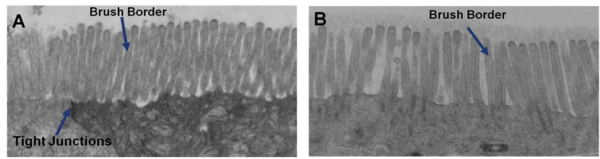

EpiIntestinal Full Thickness (SMI-FT) is a 3D reconstructed tissue model produced from normal, human cell-derived small intestine epithelial cells and fibroblasts. The highly differentiated tissue model is produced at the air-liquid-interface (ALI) in easy-to-handle tissue culture inserts. Structural analysis of the tissue model demonstrates columnar shaped basal cells and Kerckring folds. Ultrastructurally, EpiIntestinal exhibits brush borders, functional tight junctions and mucous secreting granules, similar to in vivo tissue.

Transmission electron micrograph (TEM) of in vitro EpiIntestinal (A) and Explant tissues (B) showing Brush borders (situated at the luminal pole of the enterocyte) and tight junctions. Brush border – provides digestive and absorption surface; site for enzymes & transporters.